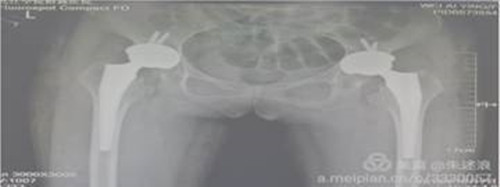

患者二十余年前开始出现髋关节疼痛,行走后疼痛加重,进行理疗、药物等保守治疗无明显效果,七个月前来临床医学院/附属医院就诊,行盆骨平片检查提示“双侧髋关节半脱位,股骨头缺血性坏死”。临床医学院/附属医院骨三科朱述浪主任带领手术团队为患者实施DAA微创手术,手术非常成功,患者在术后次日便能够负重行走,并保留正常的步态。

全髋关节置换术后康复尤为重要。在朱述浪主任的指导下,科护士长带领护理团队积极主动为患者提供康复帮助,从日常护理、助行装置使用等方面,逐步提高患者术后从事日常活动的能力。

目前患者已经康复出院,对临床医学院/附属医院高科技治疗技术及贴心优质的护理服务表示了极高的赞扬。此项技术的实施填补了九江市空白,为临床医学院/附属医院微创关节置换技术与国际接轨进一步奠定了基础。